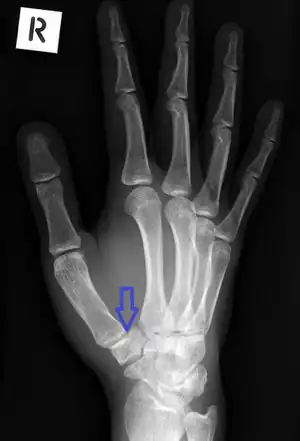

| Undisplaced fracture of the right trapezium | |

The fracture may be best seen on an oblique wrist X-ray, but some may not be visible on plain X-ray.[3] Carpal tunnel views or CT scan can be useful in unclear cases.[4]